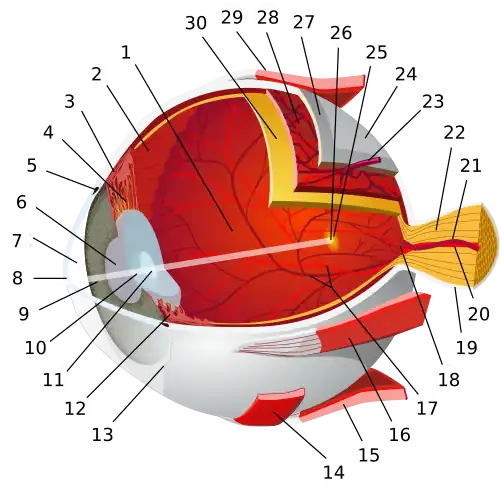

| Iris | |

|---|---|

| |

Schematic diagram of the human eye (iris labeled at upper right) | |

| Details | |

| Precursor | Mesoderm and neural ectoderm |

| Part of | Front of eye |

| System | Visual system |

| Artery | Long posterior ciliary arteries |

| Nerve | Long ciliary nerves, short ciliary nerves |